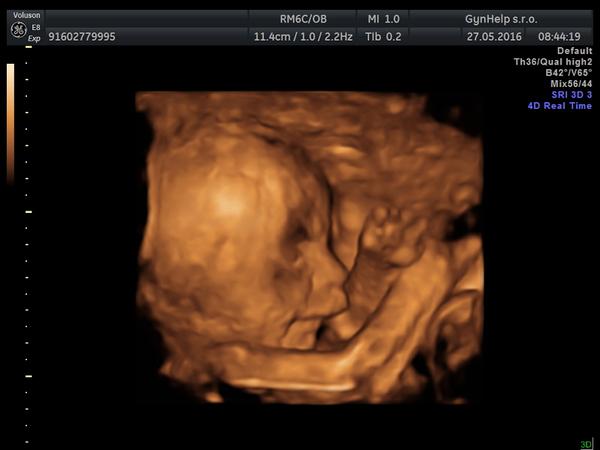

Rozštěp rtu podle 3D ultrazvuku?

ahoj holky dnes jsem byla na 3D ultrazvuku a dost som sa vydesila s pohladu na rtiky malyho,mam pocit ze neco neni v poradku.. doktorka byla neprijemna nechtela mi na nic odpovedet a tak jsem si jen vzada foto a sla :,( muzete mi prosim rict jestli je to podle fotek normalní nebo se jedna o nejaku vrozenou vadu? prosim bez blbych komentov opravdu jsem z toho spatna! dekuji moc

Podle fotek z 3D utz nelze soudit že jde o rozštěp rtu. Ale pro tvůj klid až půjdeš na kontrolu vezmi sebou foto a zeptej se na to gynekologa. Nevím jestli ta lékařka je i tvoje ošetřující gynekoložka nebo zda jsi u ní byla jen na 3D utz.

Nic to nebude,taky jsem na 3D furt viděla nějaké čárky na rtu a děsila se. Ale jsme laici a i když technologie jsou vyspělé tak to není jako obraz v zrcadle, může to být stín, různě mázlé, záleží na úhlu záběru. Buď v klidu, doktor by ti to určitě řekl.

Řekni svému gynekologovi, ať se na to provtvůj klid podívá ještě na normálním utz, tam by to mělo být vidět. Máme rozštěp v rodině, tak mě taky hlídal a z normálního utz vyloučil. Podle fotek bych řekla, že tam rozštěp není, ony ty 3D utz jsou takové celé rozvlněné, krabaté.

Tak můj manžel (MUDr) ti vzkazuje 😀 , že 3D UZ nejsou absolutně k diagnostice, že tohle je evidentně chyba toho ultrazvuku a rozhodně to neznačí rozštěp rtu. Prý jsou 3D ultrazvuky pro maminy, aby se chlubily 😀 (nedopřál mi ho.. 😀)